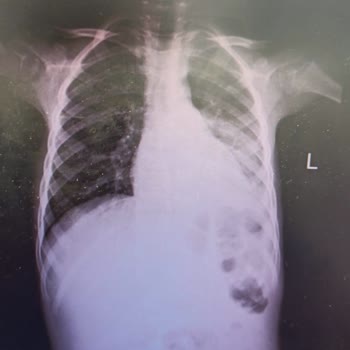

Kocaeli özel ilgi hastanesine hasta olan çoğumu götürdüm. 16 hazirandan itibaren devam eden bulantı, kusma, halsizlik, yüksek ateş şikayeti vardı. 20.06.2023 salı günü hastaneye götürdük. Dr. ** ilgilendi. Çocuğun viral hastalığı olduğunu söyledi. Ciğerlerini dinledi ama semptomlara rastlamadığını s...